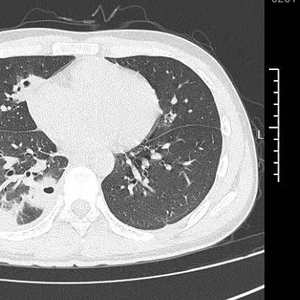

接诊的呼吸与危重症医学科丁群力主任医师一看他的症状,立刻安排了CT检查,结果显示:小林的肺里有十几个空洞,部分肺组织已经坏死,这是典型的血源性肺脓肿